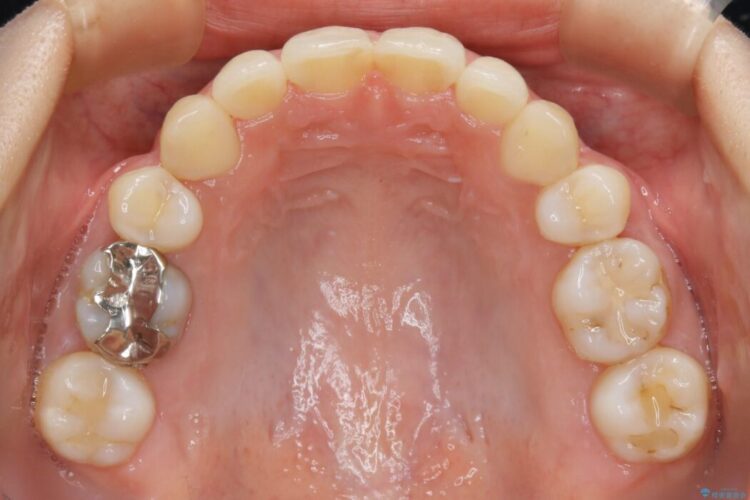

まず噛み合わせに問題が少ない奥歯の位置を極力変えないように上下左右4番目の歯を抜歯することで歯列矯正のためのスペースを確保し、空いた隙間で前歯の凹凸をきれいに並べていくこととしました。

笑った時に見えるガタついていた見栄えが改善されて歯列弓もきれいな形に整い、患者様にはご満足いただけました。